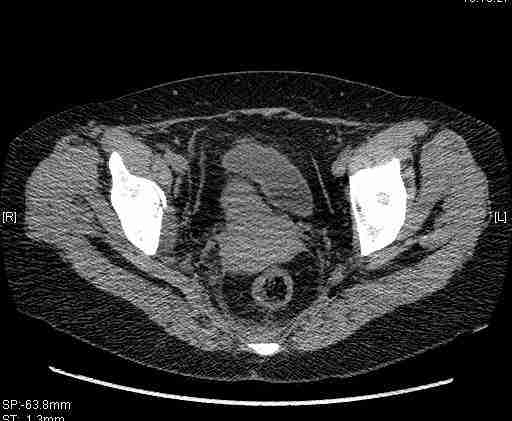

Удалось сегодня вывести пациентку в соседнюю больницу, где есть кт. Срезы сделаны только горизонтальные.

Приветствую,Антон.Рункова рядом нет,но после полученных данных КТ,обсуждали совместно.Итог обсуждения-развернутый ответ дать не получится,т.к.срезы выбраны не информативные.Если ориентироваться на данные 3D,то ,ИМХО,можно лечить на вытяжении.